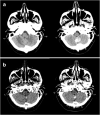

Objectives: To verify the incidence of calcified brain metastases (CBM), illustrating the different presentation patterns and histology of primary tumor.

Methods: A series of 1002 consecutive brain computed tomography (CT) scans of patients with known primary tumors was retrospectively assessed. CBM were defined by the presence of calcification within intra-axial-enhancing lesions; identification of CBM was based on visual examination and ROI analysis (> 85 Hounsfield units). Also, calcifications in the primary tumor of all patients with brain metastases were evaluated. In CBM patients, we investigated the type of calcifications (punctate, nodular, cluster, ring, coarse), the histology of primary tumor, and if a previous RT was performed.

Results: Among 190 (18.9%) patients with brain metastatic disease, 34 presented with CBM (17.9%). Sixteen patients were previously treated with RT, while 18 presented calcifications ab initio (9.5% of all brain metastases). The majority of patients with CBM had a primitive lung adenocarcinoma (56%), followed by breast ductal invasive carcinoma (20%) and small cell lung carcinoma (11.8%). CBM were single in 44.1% of patients and multiple in 55.9%. With regard to the type of calcifications, the majority of CBM were punctate, without specific correlations between calcification type and histology of primary tumor. No patients with ab initio CBM had calcifications in primary tumor.

Conclusion: In conclusion, our data show that CBM are more common than usually thought, showing an incidence of 9.5% ab initio in patients with brain metastases. This study underlines that neuroradiologists should not overlook intraparenchymal brain calcifications, especially in oncologic patients.